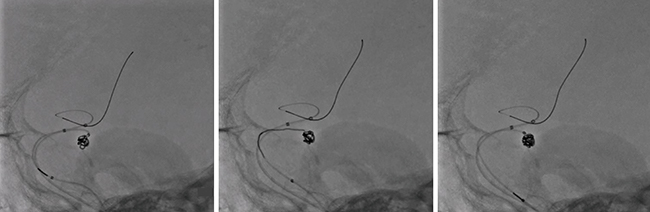

■高精細検出器(Hi-Def Detector)による3インチ拡大視野での脳動脈瘤コイル塞栓術(Angio)

Hi-Def Detectorではコイルが複数本挿入された状態でも、動脈瘤内のわずかな隙間まで描出することが可能となる。

Alphenixに搭載された高精細検出器のHi-Def Detectorは、ピクセルサイズ76μmと従来の検出器(150~200μm)よりも精細化されている。これによって、より高精細な画像による手技が可能になり、未破裂脳動脈瘤に対するコイル塞栓術の治療精度や安全性の向上が期待できる。未破裂脳動脈瘤の治療を数多く手掛けている佐藤部長はAlphenixのHi-Def Detectorについて、「従来の透視画像に比べて、解像度が格段に向上しています。コイルを詰めた瘤内の状態がはっきりと見えることはもちろん、透視画像では写らないとされていたステントの構造まで確認できます。また、Cアームの操作性なども良く、安心して手技に集中できます」と評価する。瘤内のコイルの状態がより細かく確認できることで、密度の高いコイリングが可能になり、治療の質と安全性の向上につながっている。佐藤部長は、「コイルは十分パッキングした方が、コンパクション(再開通)が減って治療効果の向上が期待できます。Hi-Def Detectorでは、瘤内の視認性が向上して隙間のないコイリングが可能です。Hi-Def Detectorは、従来の血管撮影装置よりも優れた高解像度が得られ臨床的な有用性も期待できるので、脳血管内治療を実施する施設では欠かせない装置になると思います」と評価する。